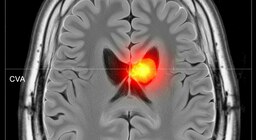

11. Vacunas con beneficios más allá de la infección